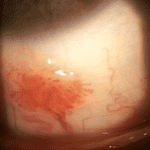

LatestPhoto Essay – A Spiral Illusion: An Atypical Presentation of Schlaegel Lines

This case describes an unusual spiral pattern of Schlaegel lines in a patient with inactive multifocal choroiditis. Although most often associated with...

Photo Essay – A Spiral Illusion: An Atypical Presentation of Schlaegel Lines

by Theresa Jay, OD, FAAO, Steve Njeru, OD, MS, FAAO and Melissa Chen, OD | Aug 19, 2025

This case describes an unusual spiral pattern of Schlaegel lines in a patient with inactive multifocal choroiditis. Although most often associated with...

Photo Essay – A Spiral Illusion: An Atypical Presentation of Schlaegel Lines

by Theresa Jay, OD, FAAO, Steve Njeru, OD, MS, FAAO and Melissa Chen, OD | Aug 19, 2025 | Photo Essay, Retina, Volume 3, Issue 3 | 0 |

This case describes an unusual spiral pattern of Schlaegel lines in a patient with inactive multifocal choroiditis. Although most often associated with...